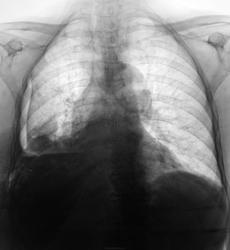

Неделю лечится в терапии, как бы по поводу сердца...

это пиопневмоторакс? или только жидкость в легком? а слева на уровне дуги аорты что? нет ли там чего-нибудь посерьезней, чем инфекция?

Хочется переломов рёбер, ключицы, всё справа, но как-то не очень внятно... а жаль!smiley Тогда причина и следствие так аккуратно вписывались бы в картину!

А это в плевре, или, скорее, в легком? Эмпиема, или абсцесс?

клиники эмпиемы нет,осумкованный пневмоплеврит.

1.Пневмоплеврит (pneumopleuritis; пневмо‑ (Пневмо-) + Плеврит) экссудативный плеврит, при котором в плевральной полости наряду с экссудатом скапливается воздух; развивается при наличии бронхоплеврального свища или как осложнение искусственного пневмоторакса.

2.Эмпиема плевры (пиоторакс, гнойный плеврит) — скопление гноя в плевральной полости. Как правило, эмпиема плевры развивается в связи с инфекционным поражением лёгких (пневмонией) и часто ассоциирована с парапневмоническим выпотом. Различают три стадии эмпиемы: экссудативная, фибринозно-гнойная и организующая. При экссудативной фазе происходит накопление гноя. Фибринозно-гнойная стадия проявляется осумкованием плевральной жидкости с формированием гнойных карманов. В конечную, организующую стадию, происходит рубцевание плевральной полости, которое может привести к замуровыванию лёгкого.

Как то не очень это на пневмоплеврит смахивает. да и где соответствующий анамнез?

А клиника может быть разной, ведь эмпиема может быть и хронической.

гидропневмоторакс справа , смещение горизонтальной м/д щели кверху , левый рёберно-диафрагмальный синус уплощён - нельзя искл. небольшое кол-во жидкости и в левой плевральной полости.

Травмы не было.

Вы правы уважаемый Виктор Григорьевич!

"Это" мало смахивает на пневмоплеврит, ну просто, аж никак.

Если не было пункции, то откуда воздух? Или из бронха (деструкция), или сами бактерии вырабатывают. В любом случае похоже на эмпиему.

Пневмогидроторакс осумкованный, эмпиемы клиника несоответствует. В месте темном мы оказались… Знания осветили бы наш путь. Темной стороны страшусь я.

Рак плевры? Взять жидкость на цитологию!